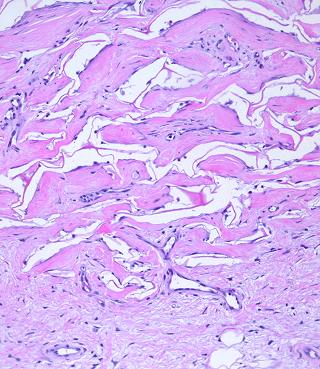

Figure 11   (top)

(a, left)  Fibroplasia in a normal wound.  This is the zone of  fibrous consolidation.  Densely packed fibroblasts are making thick chords of collagenized scar.  As the process evolves, increasing connective proteins will make the scar progressively less compliant or distensible.  These fibrous chords are multidirectional at their inception, but subjected to tensile loads, they will reorient themselves to resist that load, distorting features and obstructing motion.

(b, right)  Integra collagenization.  Cellularity is low.  Collagen conforms to the matrix, forming discrete packets molded within the pores of the sponge.  Spaces and interruptions, incoherence, between collagen clusters mean that the material remains more fluid and deformable, more like normal tissue, less like scar.